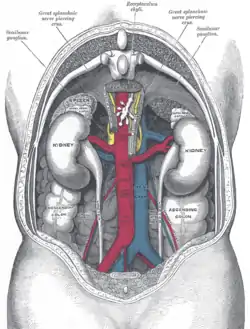

The celiac ganglia with the sympathetic plexuses of the abdominal viscera radiating from the ganglia. The relations of the viscera and large vessels of the abdomen. Seen from behind, the last thoracic vertebra being well raised.

The relations of the viscera and large vessels of the abdomen. Seen from behind, the last thoracic vertebra being well raised. Thoracic splanchnic nerves